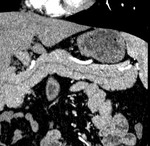

[画像診断]側頭骨骨折について 2010-08-16